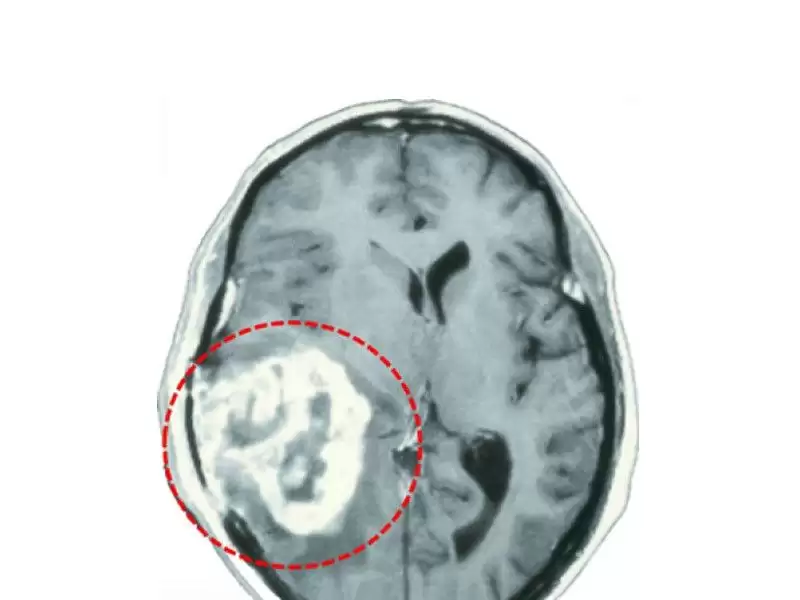

Glioblastoma multiforme, beyin tümörlerinin içinde en sık rastlanan ve tedavisi en zor olan beyin tümörüdür. Genellikle 40-60 yaş arasında ve erkeklerde daha fazla görülmektedir. Glioblastomada en sık görülen belirtiler baş ağrısı, hafıza kaybı, havale ve davranış değişiklikleridir.…

Beyin metastazı, beynin dışındaki doku ve organlarda gelişen bir kanserin beyin dokusuna yayılması ve orada da tümör oluşturması demektir. Beyinde en sık rastlanan tümörler bu tip tümörlerdir.…

Beyin, beyin sapı ve beyincikte, beyni çevreleyen zarlarda , gelişen tümörler genel anlamda beyin tümörleri başlığı altında incelenir. Yine vücudun başka bir yerinde gelişen tümörler kan veya komşuluk yolu ile beyin, beyin sapı ve beyinciğe giderek burada büyüyebilir ve bu tümörler metastatik tümörler olarak isimlendirilir.